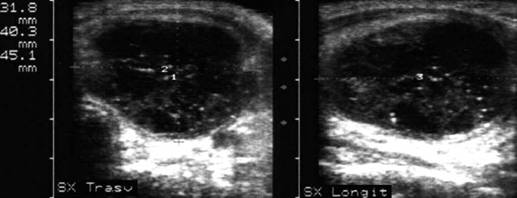

Sonda convexa de 5.0 MHz,

Sonda liniara de 10.0 MHz, proiectie trasversala si longitudinala a lobului

stang.

Pacienta de 28 ani. Voluminoasa tumefactie a lobului

stg., marcant hipoecogena, cu intarire posterioara, de 38x45x69mm.

La aspiratie, circa 60 cc de coloid foarte dens.